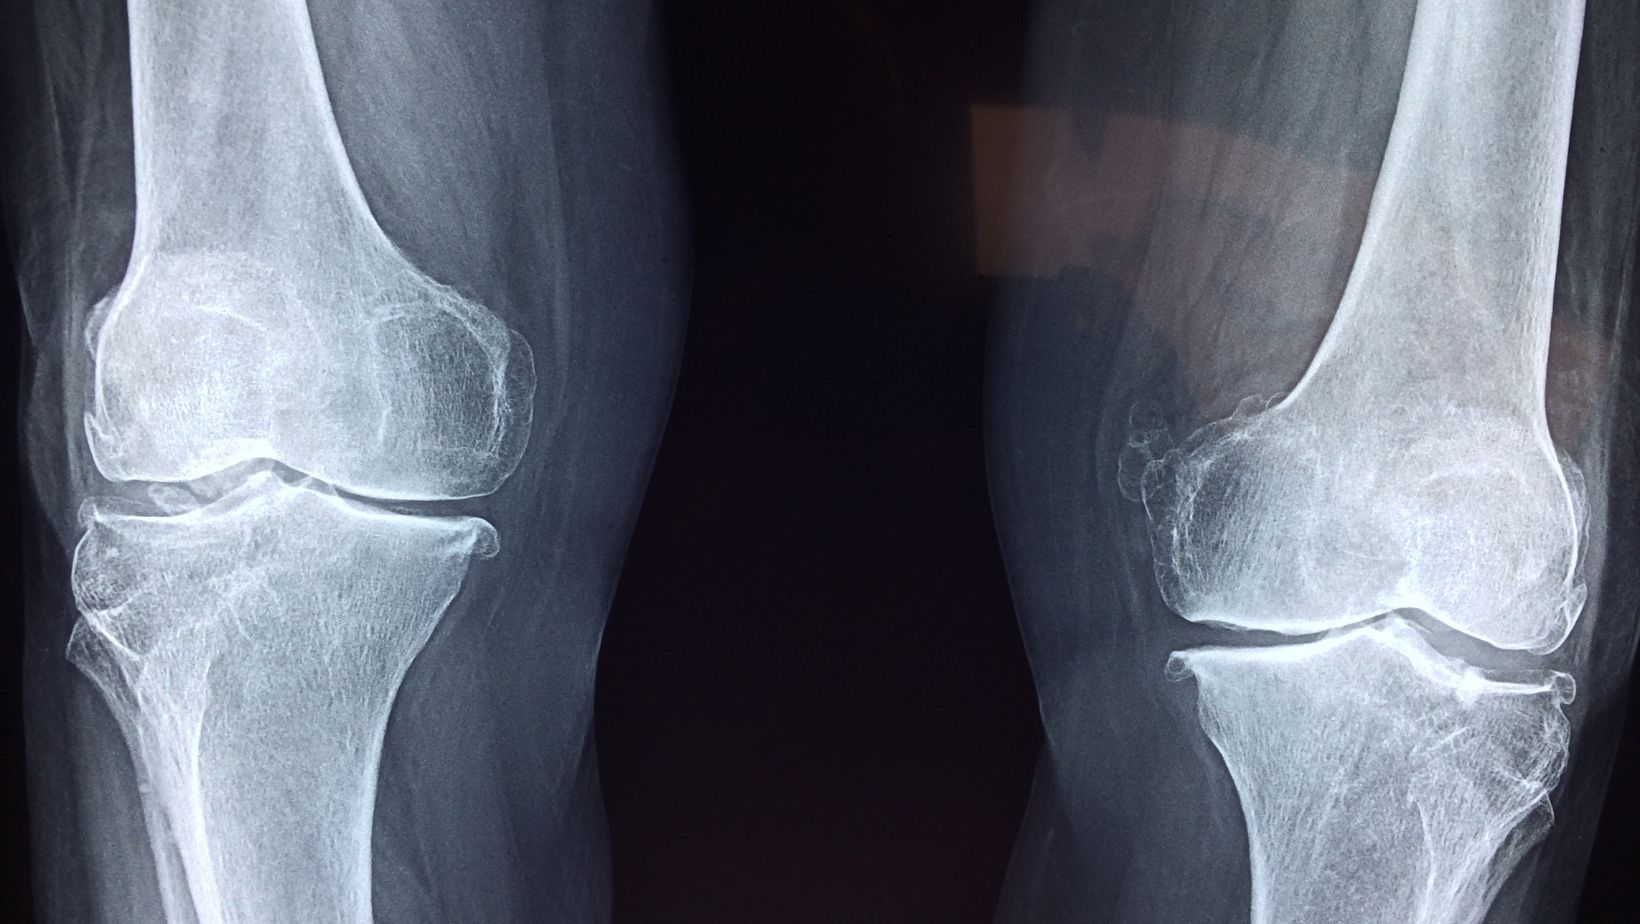

A doctor will typically begin with a physical exam and may order X-rays to rule out common causes like injury or inflammation. If something unusual appears, further testing such as MRI, CT scans, or blood work may be recommended.